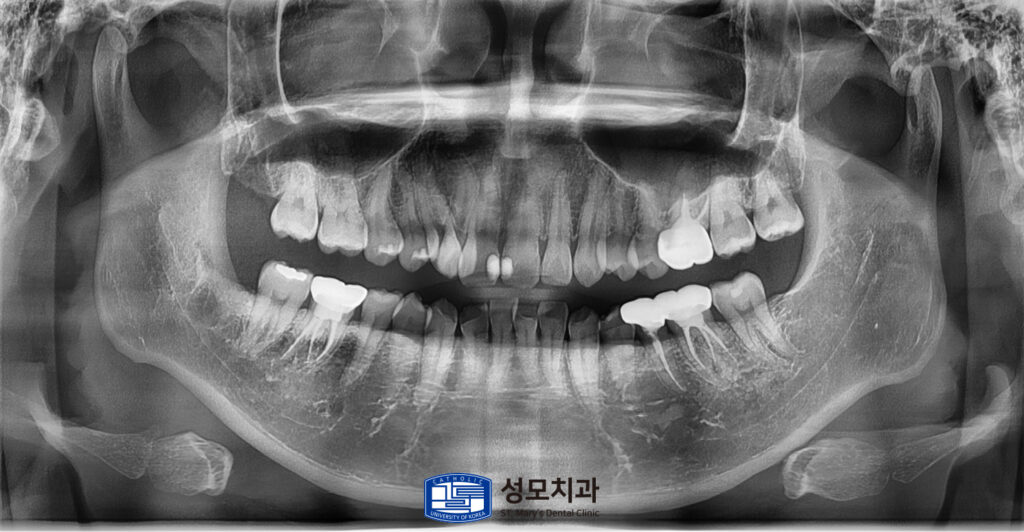

4. 치료 후 파노라마 사진

최종 치료가 완료된 파노라마 x-ray사진입니다.

치료 결과 발치가 유력해 보였던 치아는

근관치료와 코어, 크라운 조합으로

기능과 내구성을 회복했고 코어만 있던

두 치아도 최종 크라운으로 마무리되어

파절과 탈락의 위험이 크게 줄었습니다.

전치부 인접면은 레진 수복으로

자연스러운 색과 형태를 되찾아

심미적인 만족도가 높았습니다.

5. 치료 후 15개월 경과 관찰 파노라마 사진

치료가 끝나고 15개월이 지난 후

촬영한 파노라마 x-ray 사진입니다.

경과 관찰을 위해 내원해 주셨으며,

치료 부위가 모두 안정적이게 회복되어

사용 시 불편이 없다고 말씀해 주셨습니다.